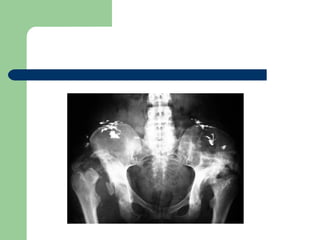

HIP

 Charcot neuroarthropathy in the hip is rare.

 Painless and Functional: no treatment

 Try conservative management

 50% of fractures of the femoral neck in

diabetics developed Charcot's joints.

HIP  Charcot neuroarthropathyin the hip is rare.  Painless and Functional: no treatment  Try conservative management  50% of fractures of the femoral neck in diabetics developed Charcot's joints.